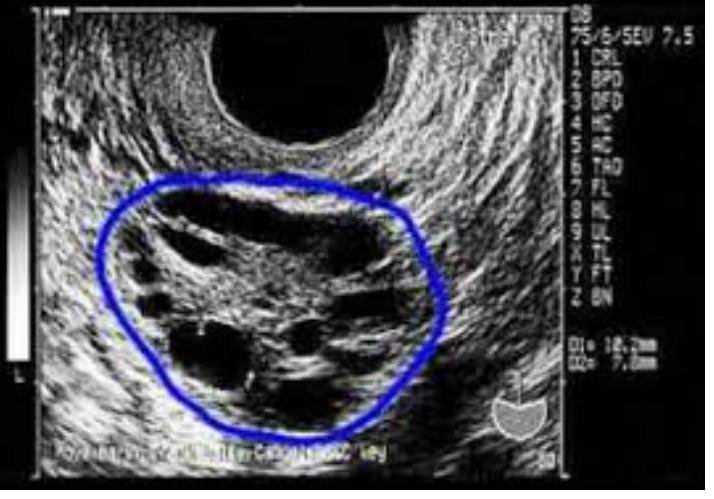

# SÍNDROME DE OVARIO POLIAÚSTICO ## DEFINICIÓN El Síndrome de Ovarios Poliquísticos (SOP) es un síndrome de disfunción ovárica, caracterizado por un hiperandorgenismo clínico o bioquímico, alteraciones menstruales, casi siempre acompañado por alteraciones ováricas identificadas por ultrasondio (poliquistosis). Fue descrito por Stein y Leventhal en 1935. Es un ESTADO DE ANOVULACIÓN CRÓNICA que se relaciona con una producción anormal de estrógenos y una secreción inadecuada de gonadotropinas, con un aumento de la sensibilidad a los pulsos rápidos de GnRH. ## EPIDEMIOLOGÍA - Aproximadamente el 6-10% de las mujeres en edad reproductiva tienen alguna forma de SOP. - Es la principal causa de oligo/anovulación crónica y de esterilidad en el primer mundo. - Los hallazgos incidentales en USG aparecen en 33 % en mujeres asintomáticas. - En el 35 % de los casos coexiste resistencia a la insulina. Complicaciones: Subfertilidad, Diabetes Gestacional, Enfermedad Hipertensiva, Sx Hiperestimulación Ovárica. El SOP Predispone a las siguientes enfermedades: - Síndrome Metabólico - Hiperplasia y Cáncer Endometrio (por oligo y amenorrea sostenida). - Hipertensión en el embarazo y Preeclampsia - Diabetes Mellitus Tipo 2 - (realizar detección ANUAL de alteraciones en el metabolismo de carbohidratos si hay intolerancia a la glucosa) - Diabetes gestacional - Enfermedades Cardiovasculares - Parto Pretérmino. ## FACTORES DE RIESGO - Obesidad y sobrepeso - Antecedente familiar primer grado # FISIOPATOLOGÍA Las dos principales anormalidades hormonales en el SOP son: - ELEVACIÓN DE LH - ELEVACIÓN DE INSULINA. 1. Existe un sinergismo de la elevación de ambas hormonas, lo cual termina por provocar atresia folicular e incapacidad para la formación de estrógenos en el ovario. 2. La hiperestimulación ovárica por la insulina provoca el hiperandrogenismo. 3. Se han identificado en el ovario humano receptores para la insulina y los factores de crecimiento similares a la Insulina Tipo 1 (IGF-1), los cuales son homólogos de los receptores de insulina en un 40 %, pero con menor afinidad, se unen a ella en presencia de ciertas patologías que cursan con estados de resistencia a la insulina e hiperinsulinemia compensatoria. 4. En un círculo vicioso, la HIPERINSULINEMIA incrementa formación de receptores IGF-1 y la hipófisis también tiene receptores para la insulina, por lo que teniendo un estímulo de la insulina, incrementa secreción de LH. 5. La hiperinsulinemia inhibie la producción de la proteína transportadora de hormonas sexuales, lo cual aumenta la proporción de testosterona libre, que a su vez representa la orma activa de la hormona. 6. La conversión periférica de andrógenos a estrona inhibe la secreción de FSH, llevando a ciclos anovulatorios. 7. El eje hipotálamo-hipófisis-adrenal está involucrado en el SOP (40-70%) en donde se elevan los andróngenos suprarrenales circulantes con respuesta inapropiadamente alta durante las pruebas de estimulación con ACTH. 8. Puede tener relación con la elevación de la enzima ovárica Citocroma P450c17 alfa, la cual se relaciona con la biosíntesis de andrógenos e incrementa los niveles de 17-alfa-hidroxiprogesterona.  # CLÍNICA - INFERTILIDAD: Es la afección que más frecuentemente refieren (causada por anovulación). - TRASTORNOS MESTRUALES - Fluctuan durante la pubertad hasta llegar a OLIGOMENORREA o AMENORREA ## EXPLORACIÓN FÍSICA - Obesidad típicamente androide - Hirsutismo - Acné - Alopecia androgénica ## ESCALA DE FERRIMAN Y GALLAWAY  Datos de Resistencia a la Insulina: - Acantosis nigricans - Zonas hiperpigmentadas en nuca, axilas o ingles # DIAGNÓSTICO Existen diversos criterios planteados por consensos y sociedads que se utilizan para diagnosticar el SOP. ## CRITERIOS DEL NIH (recomendados por la GPC) 1. Hiperandorgenismo clínico o hiperandrogenemia 2. Oligoovulación o anovulación 3. Exclusión de trastornos relacionados a Hiperandrogenismo (hiperprolactinemia, desordenes tiroideos, hiperplasia adrenal congénita, tumores secretores de andrógenos, Sx Cushing, deficiencia de 21hidroxilasa, hiperplasia adrenal no clásica, uso de drogas anabólicas o andrógenos, Sx resistencia a la insulina severa) ## CRITERIOS DE AE / PCOS SOCIETY Hirsutismo o Hiperandrogenemia Disfunción ovárica: Ologio o anovulación y/o Ovarios Poliquísticos Exclsuión de trastornos relacionados a hiperandrogenemia ## CRITERIOS DE ESHRE/ASRM (DE ROTERDAM) Debe incluir 2 de las siguientes 3 características, después de la exclusión de otros trastornos relacionados: 1. Oligoovulación o Anovulación 2. Datos clínicos o bioquímicos de hiperandrogenismo 3. Ovarios Poliquísticos por imagen ## ESTUDIO DE IMAGEN ## ULTRASONIDO PÉLVICO Presencia de 12 o más folículos Con diámetro 2-9 mm  Volumen Ovárico +10ml # ESTUDIOS HORMONALES La medición sérica de andrógenos, incluyendo la testosterona libre debe ser usada solo como herramienta coadyuvante de trastornos hiperandrogénicos y no como criterio único de diagnóstico.  ## LH/FSH - La LH se eleva y estimula la producción de andrógenos por las células de la teca, provocando un aumento de la androstenediona y testosterona de origen ovárico (causando atresia de folículos en desarrollo) - La conversión periférica de andrógenos provoca aumento de Estrógenos, ihibiendo liberación de FSH. - Relación LH/FHS > 2.5 ## TESTOSTERONA TOTAL - Puede estar normal o moderadamente elevada en el SOP. - En niveles superiores de 60 ng / dLL es sospechoso para SOP. - Nivel elevado: realizar prueba de 17-hidroxiprogesterona para descartar otro origen. ## GLOBULINA FIJADORA DE HORMONAS SEXUALES (SHBG) - Es normal o tiende a la baja en mujeres con SOP (menor a 3.4 nmol / L ) - Porporciona una medida sustituta del grado de hiperinsulinemia. ## ÍNDICE DE ANDRÓGENOS LIBRES - Este es normal o elevado en mujeres con SOP (normalmente es inferior a 5) - Porporciona evaluación de la cantidad de testosterona presente fisiológicamente activa. ## INSULINA Se presenta una hiperinsulinemia, secundaria a la resistencia de insulina. - No se considera diagnóstico pero la identificación permite conocer aquellas pacientes que se beneficiaran de la reducción de insulina. - Se recomienda realizar carga oral de glucosa con 75 gramos. ## SÍNDROME METABÓLICO | Presión Arterial | >135 / 80 | | :--: | :--: | | Circunferencia De Cadera | >90 ~cm | | Glucosa En Ayuno | >100 | | HDL | <50 | | Triglicéridos | >150 | - Evluar perfil de Lípidos ABORDAJE PARACLÍNICO: LH, FSH, Testosterona Totla, Dehidroepiandrosterona, Curva de Tolerancia a la Glucosa, Progesterona, Prolactina, TSH. # TRATAMIENTO ## 1ra elección: DIETA Y EJERCICIO - Indicado en mujeres con sobrepeso y SOP. Debe iniciarse previo al uso de inducción a ovulación. - Reduce el hiperinsulinismo e hiperandrogenismo - Reduce el riesgo de DM2 y enfermedad cardiovascular - Regulariza la menstruación ## METFORMINA - Mejora la sensibilidad a la insulina, con beneficios para las tasas de ovulación y embarazo, sin embargo, no se recomienda como manejo único para la ovulación. - Disminuyen concentración de LH. ## INFERTILIDAD ## ANTIESTRÓGENOS ## 1ra elección: CITRATO DE CLOMIFENO - Aumenta la ovulación y las tasas de embarazo. - Usar durante \mathbf{1 2} meses en pacientes con deseo de embarazo. - Otro: TAMOXIFENO (si hay resistencia - Gonadotropinas sintéticas (FSH) ) - OBJETIVO: generar NO MÁS DE 3 FOLÍCULOS con posibilidad de ovular en cada ciclo inducido con el fin de minimizar el riesgo de Síndrome de Hiperestimulación Ovárica o Embarazo Múltiple. ## HIRSUTISMO Se tuilizan antiandrógenos en combinación de anticonceptivos orales. ## 1ra elección: ACETATO DE CIPROTERONA + ETINILESTRADIOL. - Es un potente progestágeno de larga acción que inhibe la liberación de Gonadotropina y compite por la unión con los receptores de andrógenos. Debe darse combinada como píldora anticonceptiva. - Indicado para Hirsutismos Leves. OTROS: - FLUTAMIDA: antiandrogénico no esteroideo que carece de otra actividad hormonal. Efecto secundario Hepatotoxicidad. - Epironolactona: efectivo para disminuir el grado de hirsutismo. - Finasterida: Bloqueador 5-alfa reductasa, responsable de convertir testosterona en dihidrotestosterona (escasos efectos secundarios, pero no mayor efecto anti hirsutismo) Efecto en feto: FEMINIZACIÓN DE FETOS MASCULINOS Ante cualquier tratamiento antiandrogénico en mujeres fértiles, debe asegurarse la anticoncepción efectiva para evitar riesgo de feminización de feto masculino. Los antiandrógenos de efecto prolongado deben suspenderse al menos 2 meses antes de buscar el embarazo. # PROFILAXIS CÁNCER DE ENDOMETRIO La oligo o amenorrea se asocia a hiperplasia y cáncer de endometrio. - Iniciar PROGESTÁGENOS para inducir hemorragia por deprivación por lo menos cada 3 - 4 meses en SOP. ## QUIRÚRGICO ## Cirugía Laparoscópica con Diatermia o Laser - Destrucción ovárica parcial con cauterización o láser vía laparoscópica (disminuye porducción andrógenos), pequeñas incisiones en el ovario para disminuir la cuenta folicular. - Está indicado para inducir la ovulación en pacientes que no responden al tratamiento con Antiestrógenos o que serán sometidas a laparoscopía. Efectos secundarios: adherencias y falla ovárica prematura.